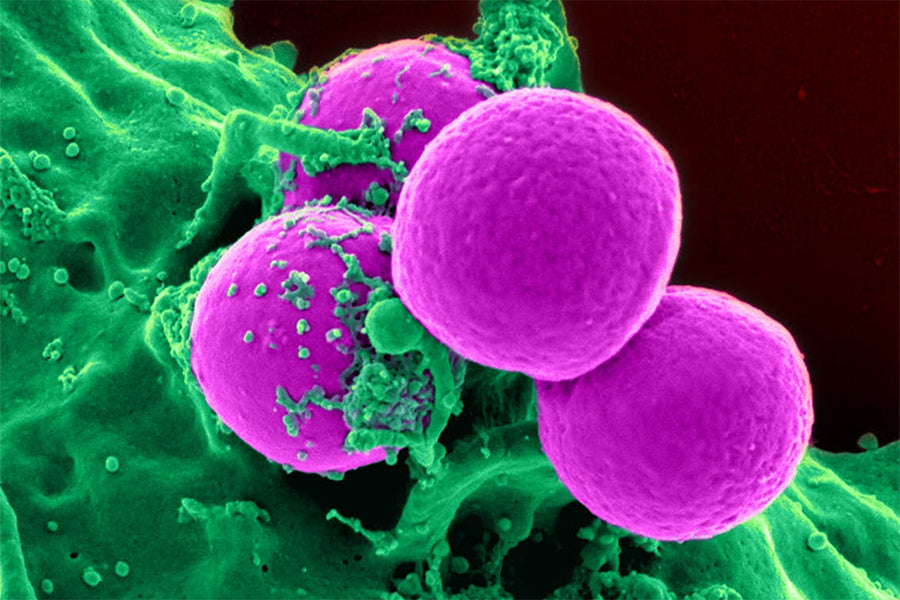

JAK Inhibitors – Could they treat your hair loss?

JAK stands Janus Kinase which are a family of enzymes that are used to transmit signals within the body along particular pathways. We won’t confuse with a more detailed description of what Janus Kinase enzymes do, as the complex terminology...